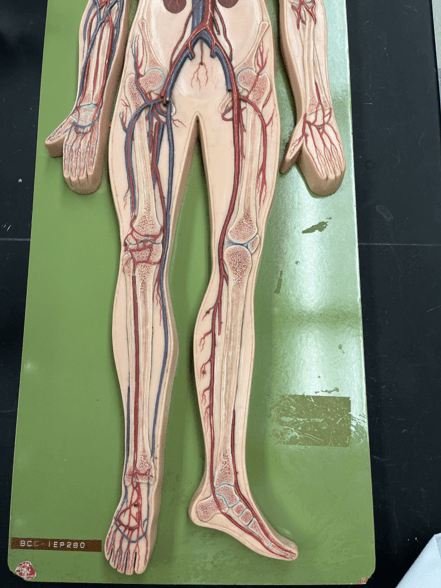

11

New cards

endothelium

• Part of the tunica interna.

• Composes a smooth inner surface of the vessel.

• Composes a smooth inner surface of the vessel.

12

New cards

valve

• Found in some veins.

• Establishes unidirectional flow of blood.

• Establishes unidirectional flow of blood.

13

New cards

common carotid artery

• An artery of the head and neck.

• Originates from the brachiocephalic trunk (R.) or the aortic arch (L.).

• Supplies the head and neck through its branches.

• Originates from the brachiocephalic trunk (R.) or the aortic arch (L.).

• Supplies the head and neck through its branches.